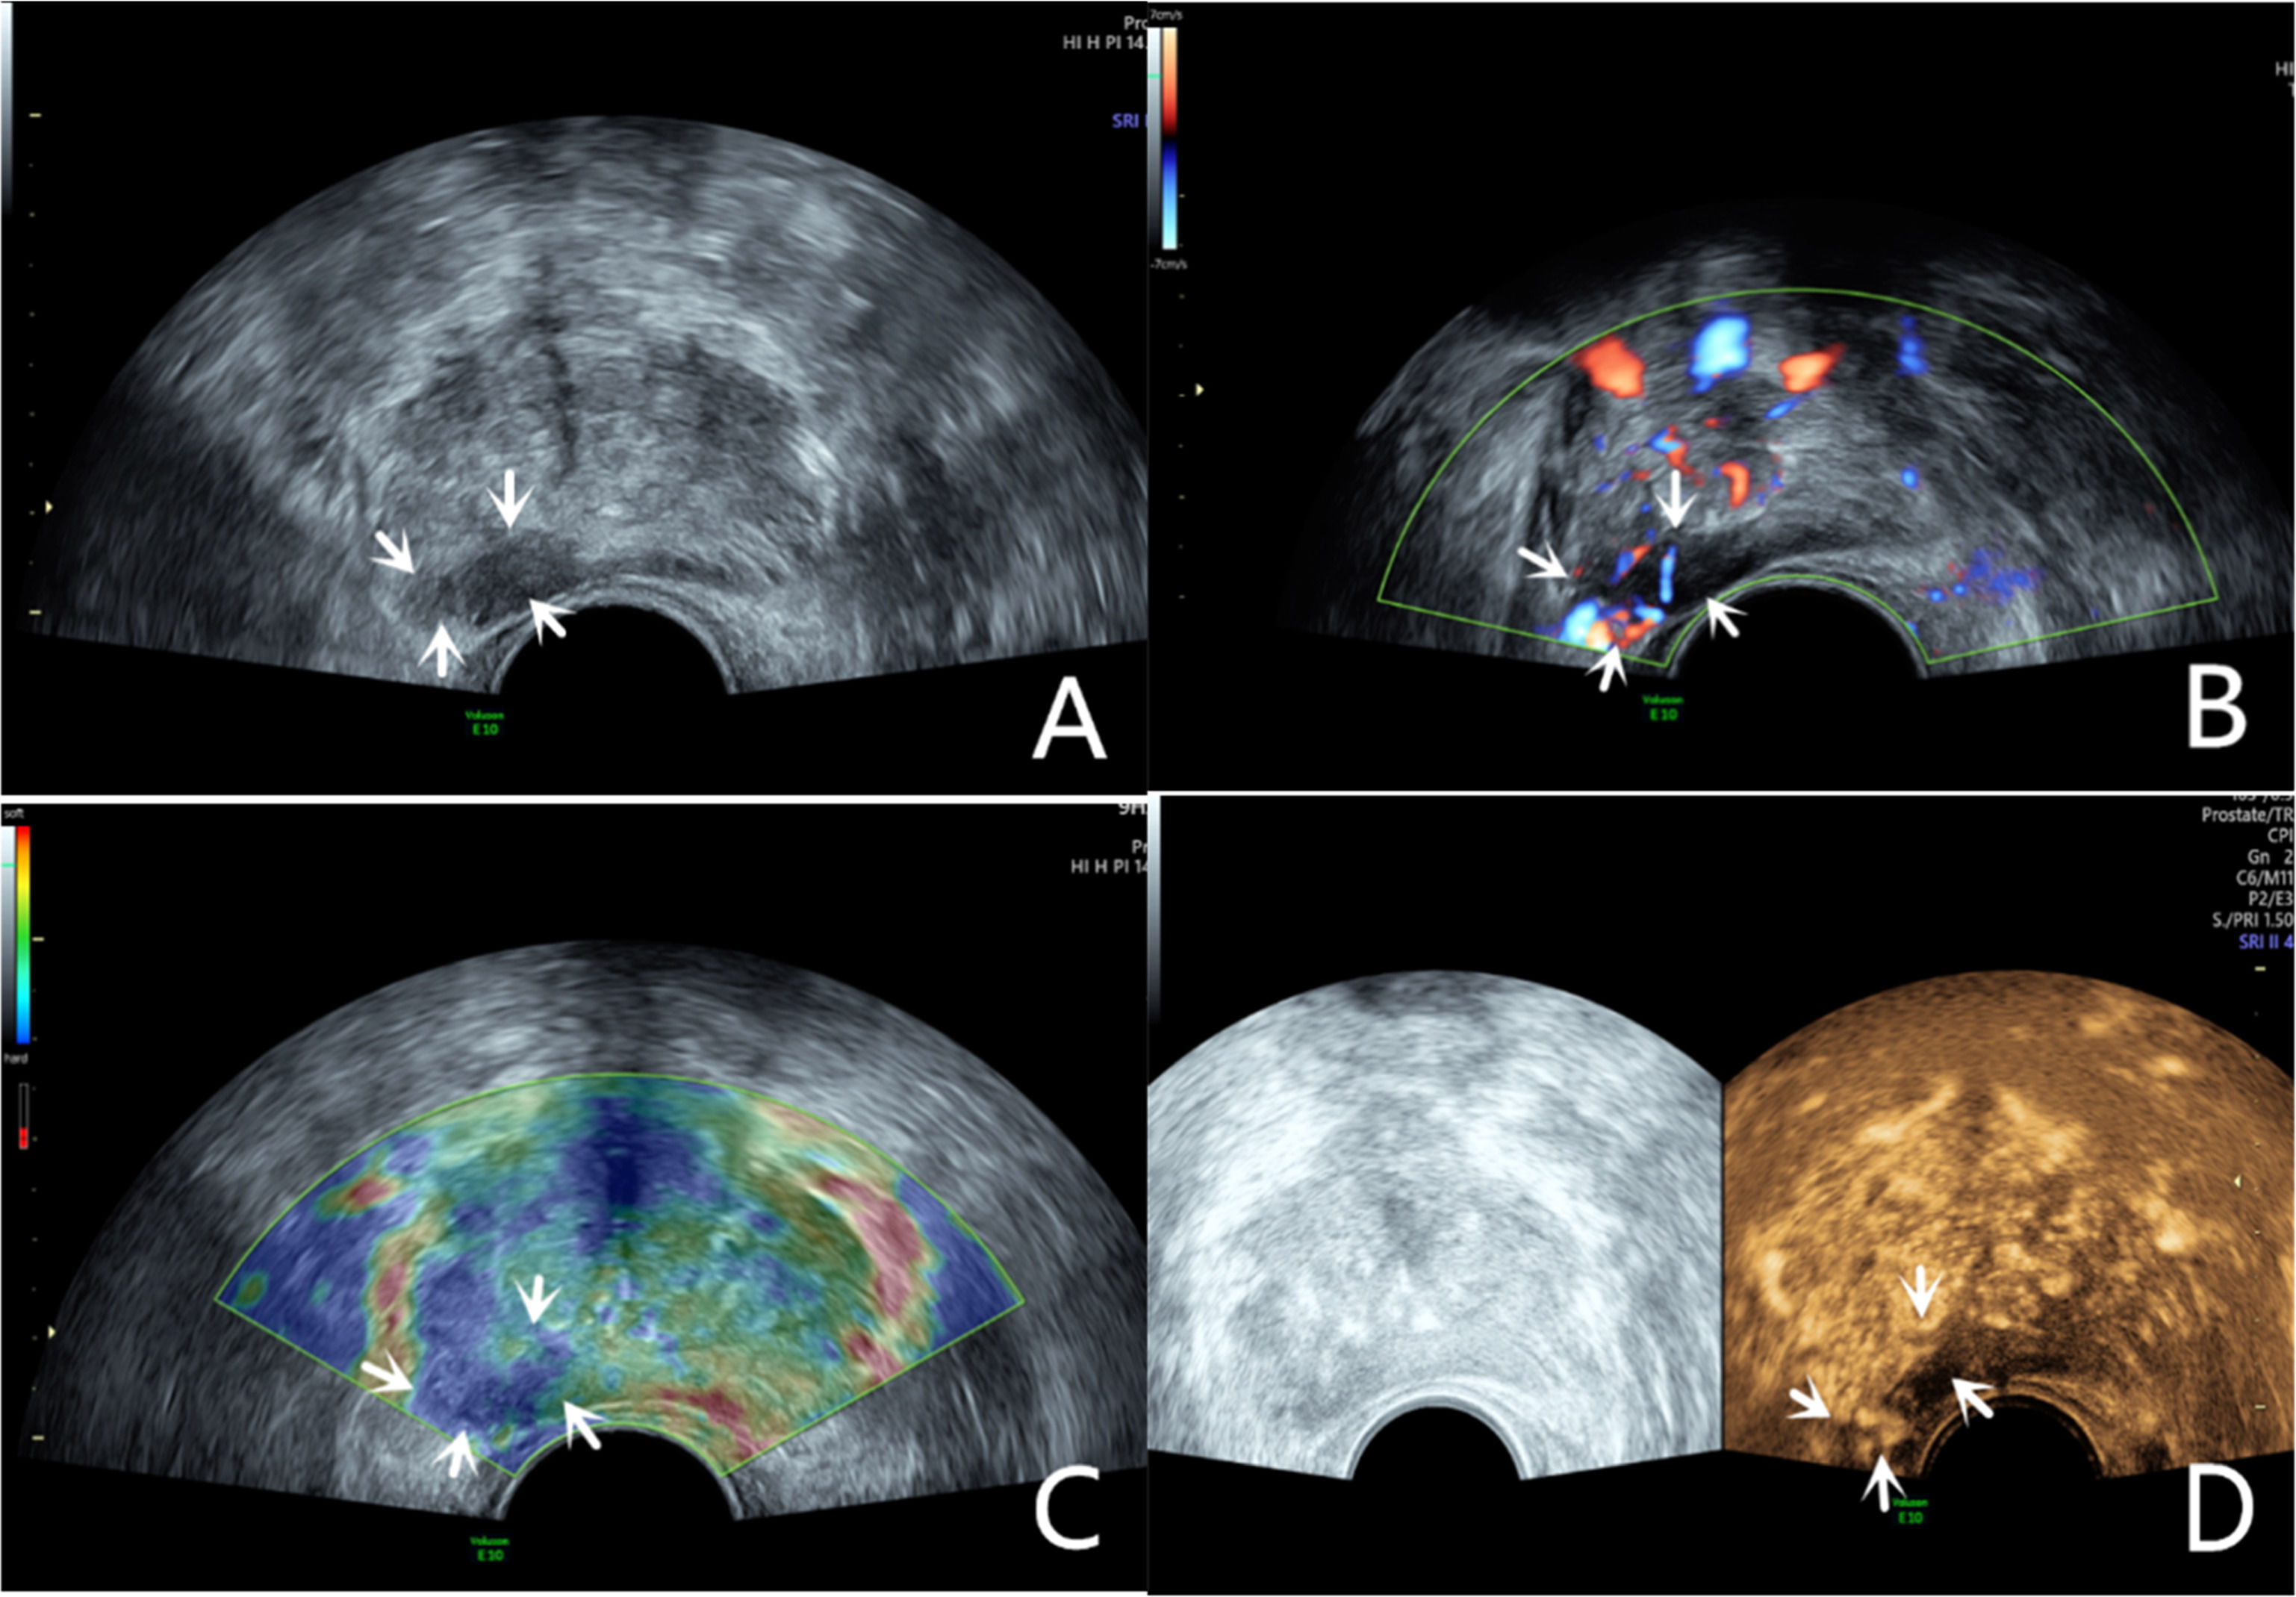

Grayscale ultrasound examinationTransrectal GSU was routinely performed using a GE Voluson E10 ultrasound system (GE Healthcare, Milwaukee, WI, USA) with a 3.5‒8 MHz rectal convex array probe (RIC 5–9-D). Before the examination, the patients were asked to empty their bowels and were positioned in a left lateral decubitus position. Then, a sonographer inserted the probe into the patient's rectum and preliminarily evaluated the shape, size, internal parenchymal echo, and integrity of the capsule of the prostate through multiple views, such as longitudinal and transverse sections. The criteria for GSU were as follows: a hypoechoic lesion in the prostate parenchyma was suspiciously positive, and isoechoic or hyperechoic lesions were considered negative (Fig. 1A; Fig. 2A).10

A 76-year-old patient had a total PSA of 14.3 ng/mL. Multiparameter US started with conventional transrectal ultrasound, and the lesion was a hypoechoic nodule at the junction of the inner and outer glands in the prostate’s left lobe (A, arrow). The lesion appeared on CDU with rich blood flow in the arterial spectrum (B, arrow). The operator used the endocavitary transducer to alternate between compressing and decompressing the lesion, which appeared mostly blue on TRTE (C, arrow). A hypoechoic nodule appeared on CEUS as a hypervascular nodule with a “fast in, fast out” enhancement pattern (D, arrow). Histopathology showed that the prostate lesions were clinically significant and Gleason 4 + 3 PCa.

The lesion was a hypoechoic nodule in the outer glands of the prostate’s right lobe (A, arrow). The lesion appeared on CDU with rich blood flow (B). The operator used the endocavitary transducer to alternate between compressing and decompressing the lesion, which appeared mostly blue on TRTE (C). A hypoechoic nodule appeared on CEUS as a hypervascular nodule with hyperenhancing pattern (D).

The CDU/PDU examination of suspicious areas followed the grayscale ultrasound examination described above. The richness of blood flow in the parenchyma and the presence or absence of abnormal blood flow branches were observed. The criteria for Doppler ultrasonography were as follows: areas with rich blood flow or multiple abnormal blood flow branches compared with the surrounding normal prostate tissue were suspiciously positive, and areas with consistent blood flow or reduced blood flow compared to the surrounding normal tissue were considered negative (Fig. 1B; Fig. 2B).14

Transrectal real-time tissue elastographyBy engaging the dual display function for grayscale images and elastic images at the same time, TRTE examination on the hypoechoic area from GSU and the area with abnormally increased blood flow from Doppler ultrasound was performed. The suspicious area was placed in the sampling frame, and the probe was used to regularly and gently press the gland 1‒2 times/second with a pressure index of approximately 4. The optimal force and frequency of the manual compressions of the prostate were monitored by the visual color bar and waveform indicators. The images were frozen and stored after 3‒5 stable waveforms appeared in the elastogram. Different colors on the TRTE elastogram marked different densities of prostate tissue, with blue indicating hard tissues and red indicating soft tissues. PCa is stiffer than normal prostate tissue and often appears blue on TRTE images due to increased cell density, microvascularization, and collagen deposition from the matrix reaction. The criteria for TRTE were as follows: a blue area > 50 % in the nodule was suspiciously positive, and an area ≤ 50 % was considered negative (Fig. 1C; Fig. 2C).15

Contrast-enhanced ultrasound examinationThe microbubble suspension-based contrast agent SonoVue (Bracco Imaging SpA, Milano, Italy, 2.4 mL) was fully mixed with 5 mL of 0.9 % NaCl solution and was administered intravenously. The examination was started after the injection of the microbubble suspension and performed with a mechanical index of 0.2. Data such as contrast enhancement time, enhancement intensity, and contrast agent disappearance time in the suspiciously marked lesions of the prostate were recorded synchronously. After the contrast agent completely dissipated, the sonographer repeated the same examination again. The criteria for CEUS were as follows: early hyper enhancing areas in the prostate were suspiciously positive, and areas of simultaneous or late, isoenhancing or hypo-enhancing areas were considered negative (Fig. 1D; Fig. 2D).16 The results of all the above examinations were judged independently by two sonographers. Both sonographers are professors of ultrasonic diagnostics. The data used for the later logistic regression analysis were the results from only a senior experienced sonographer. The data for the repeatability test were additionally obtained from another sonographer with similar clinical experience who examined a random sample of patients compared to the previous sonographer.